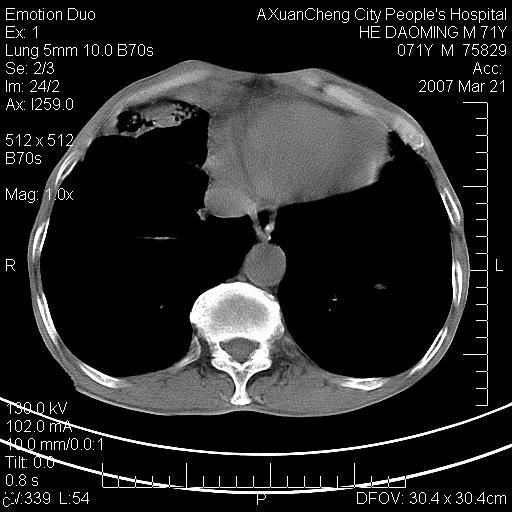

标题: CT7269:[原创] 咳嗽,咳痰,大家讨论右肺病变的部位 [打印本页]

标题: CT7269:[原创] 咳嗽,咳痰,大家讨论右肺病变的部位

1.慢支肺气肿 肺心病 肺大泡;2.叶间裂积液,前胸膜粘连

右侧相当于叶间软组织样密度ct值约50hu,请大家讨论是什么性者病变

右下肺大囊肿伴感染.肺气肿,肺大泡.

考虑:慢性支气管炎合并全小型肺气肿、肺大泡、间质纤维化、感染,右斜裂积液。

考虑慢支,肺气肿,肺大泡,间质纤维化;右侧斜裂液气胸考虑(可能因为肺大泡破裂破入斜裂所致).

考虑病变以右上中肺多发肺大泡为主并感染。请结合临床考虑慢支肺气肿,肺心病。

1双肺慢性支气管炎并全小叶型肺气肿肺大泡2间质性纤维化3右侧斜裂积液

考虑:慢性支气管炎合并右侧全小型肺气肿、肺大泡并感染、双肺间质纤维化,右斜裂积液。

考虑:慢性支气管炎合并右侧全小型肺气肿、肺大泡并感染、双肺间质纤维化,右斜裂积液。右侧斜裂液气胸考虑(可能因为肺大泡破裂破入斜裂所致).